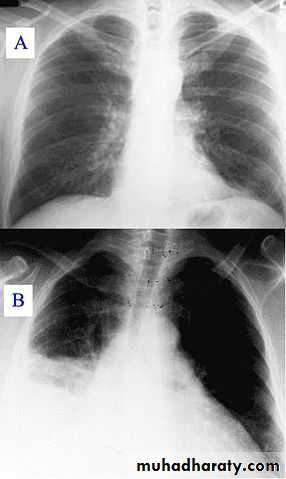

Foreign body aspiration

78% of those who die from foreign body aspiration are between 2 mo and 4 yr old.Atypical histories or misleading clinical and radiologic findings may be misdiagnosed with asthma or another obstructive disorder as inflammation and granulation develop around the foreign body.